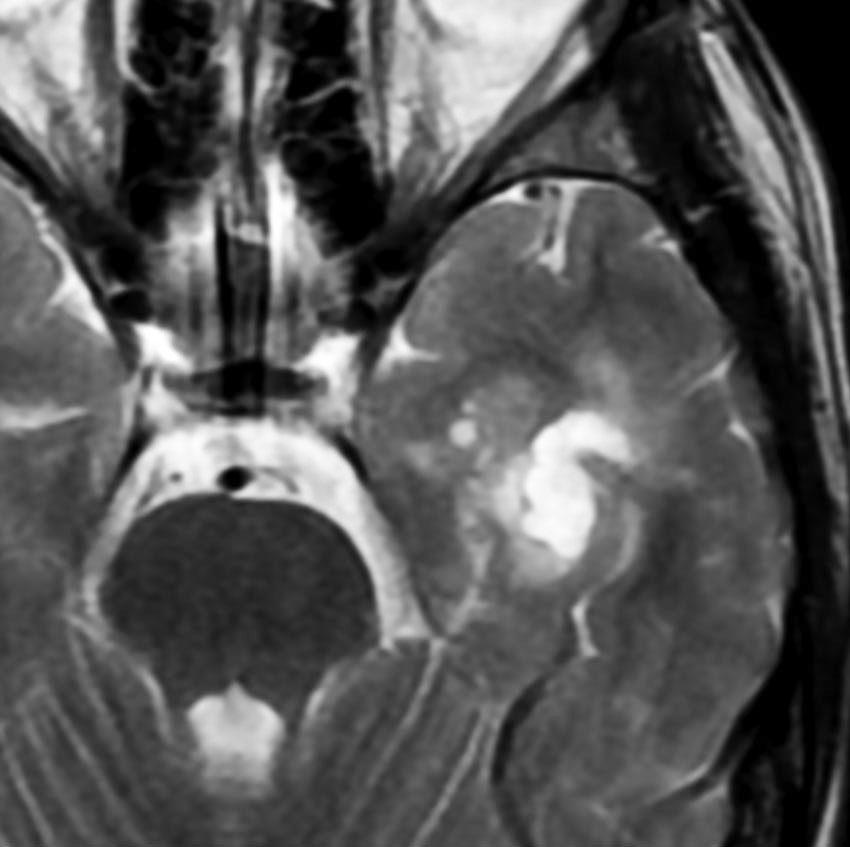

神経線維腫症1型に合併した退形成を示す anaplastic PXA

もともと停止性水頭症があり経過観察を受けていたNF-1の患者さんに発生したものです。嘔気と左片麻痺で発症しました。 開頭手術で亜全摘出(ほぼ全摘)しました。

術後に小さな腫瘍が残っていた(左の画像)ので54Gy/27frの放射線治療をしましたが,無効でした。結局,再開頭手術で残存腫瘍を摘出しました。3年後に同じ部位で再発(中央の画像)したので,また開頭手術で摘出しました。そのまた3年後に同じ部位で再発しました(右側の画像)。この様に,摘出しきれなければ治らないし,摘出できれば治る可能性の高い腫瘍です。腫瘍床での再発は多いものの,転移とか脳深部への浸潤性増殖は少ないといえる腫瘍です。放射線治療が効きにくいということを併せて,atypical meningioma WHO grade 2と似た性格を有しています。